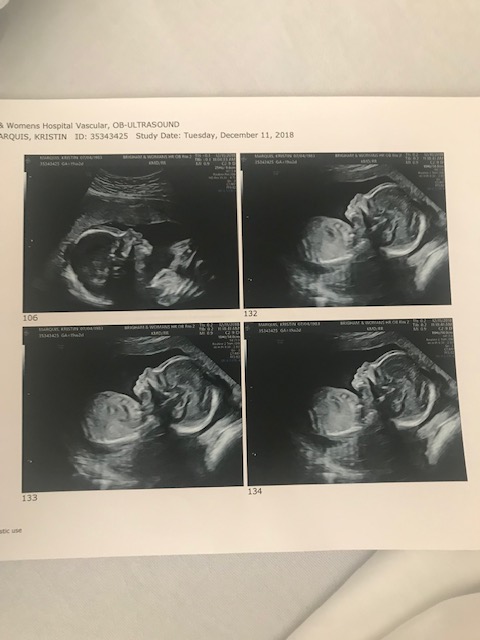

- Getting ultrasounds more often than normal (best part)

We are ready to welcome our little lady in just about 10 days! We are being induced on 4/17/19 and couldn’t be more excited!

Louise Victoria Marquis, you are so loved, so strong, and our greatest journey yet!